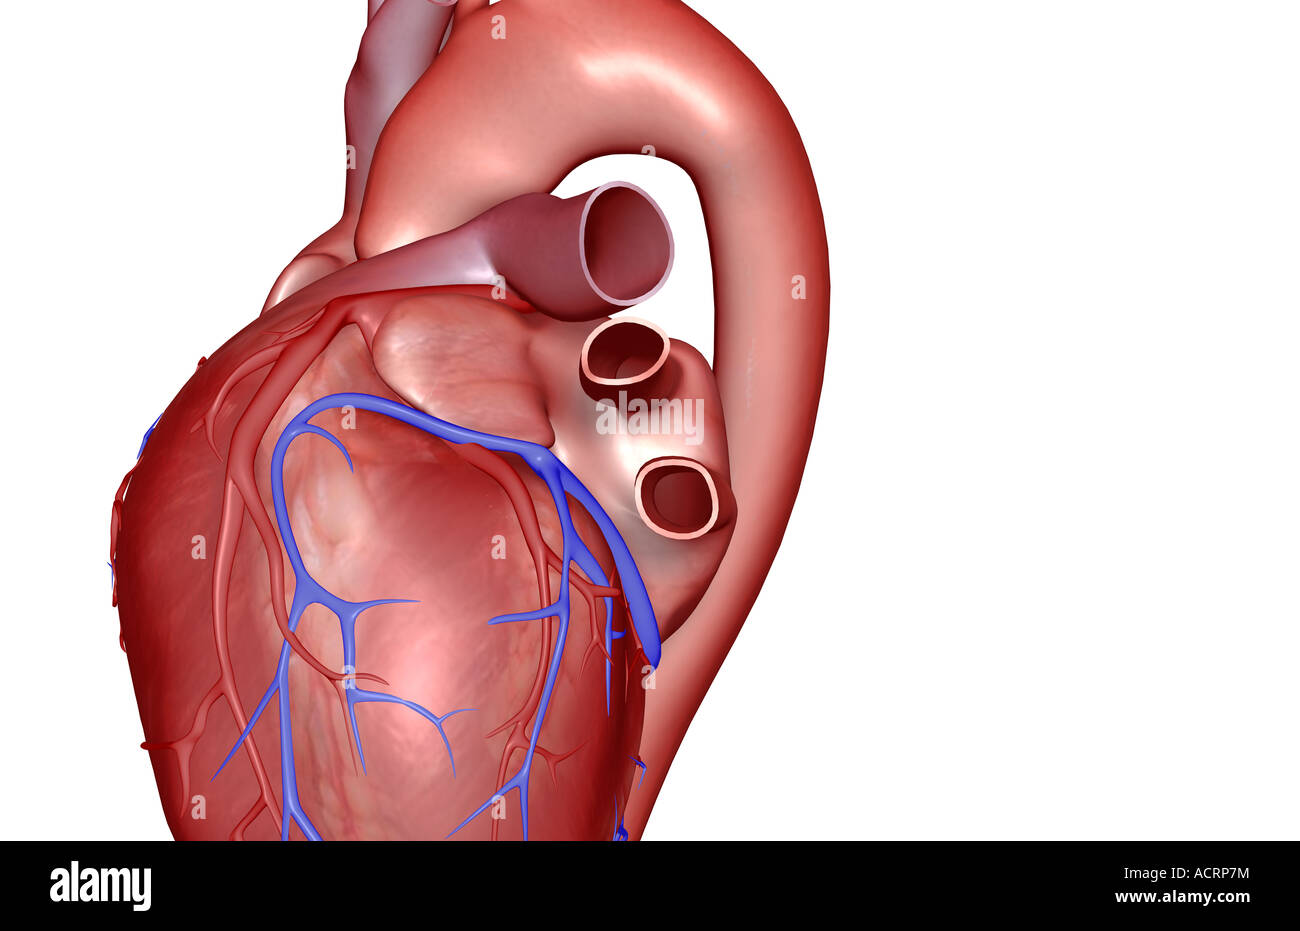

The coronary vessels of the heart Stock Photohttps://www.alamy.com/image-license-details/?v=1https://www.alamy.com/stock-photo-the-coronary-vessels-of-the-heart-13174855.html

The coronary vessels of the heart Stock Photohttps://www.alamy.com/image-license-details/?v=1https://www.alamy.com/stock-photo-the-coronary-vessels-of-the-heart-13174855.htmlRFACK1FM–The coronary vessels of the heart